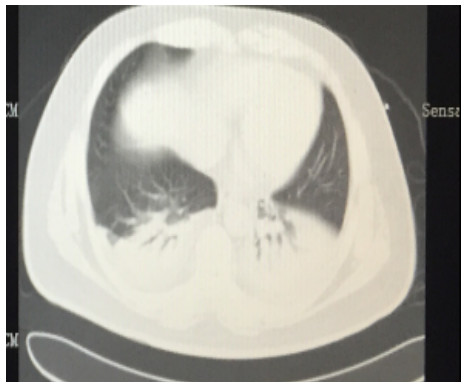

SAP发生呼吸衰竭的原因很复杂,其原因有以下几种。(1)SAP因为炎症反应导致的ARDS(图 1),这是普遍认为的一种原因,但实际上ARDS在SAP患者呼吸衰竭中很多时候是非主要原因。SAP急性期虽然病情进展很快,出现多脏器功能损伤,甚至休克,有类似于脓毒症和感染性休克样的表现,但其炎症反应并不如脓毒症这么强烈,大量的研究可见SAP发生过程其IL-6很少过千,而脓毒症则IL-6动辄大于5 000或10 000,SAP两肺影像学也很少有典型的非心源性肺水肿的双侧阴影,超声下也很少有“B线”表现。但胆道感染引起的脓毒症合并SAP的患者,其ARDS发生率会明显上升。现在随着高脂血症胰腺炎的增加,部分患者到院时同时存在糖代谢障碍,合并有糖尿病酮症,入院前后出现糖尿病酮症昏迷,有些患者会伴有呕吐误吸或者插管时误吸,这类患者在急性期会出现误吸相关的ARDS。(2)SAP是腹腔重症的一种,急性期因为腹膜后急性胰周液体积聚和急性胰周坏死物积聚,导致腹腔压力进行性升高,随之出现横膈抬高,两肺压缩,从而导致“小肺”,这和ARDS的“baby lung(小肺)”不同(图 1: ARDS;图 2、3: 腹内压14 mmHg和23 mmHg的对比,明显看到图 3呈现横膈抬高引起的小肺)。因横膈位置上抬导致小肺是SAP呼吸衰竭的主要原因。(3)两下肺不张(图 4)和胸腔积液(图 5):这两个原因也是导致SAP呼吸衰竭的主要原因,因为膈下刺激,导致两下肺的不张和大量胸腔积液常见于SAP患者,这两种原因导致的呼吸衰竭也和ARDS不同。(4)其他原因:胸腔出血、肺梗死和气胸亦可见于SAP相关呼吸衰竭,但相对少见。

| 图 1 ARDS |